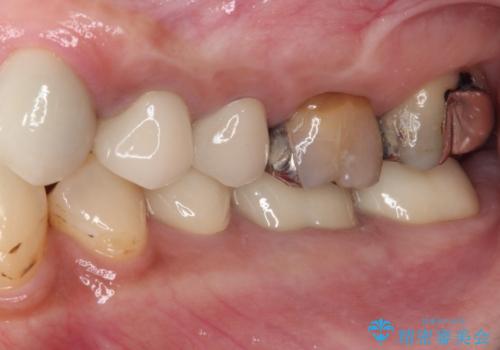

前歯の裏側の接着面は、隙間ができていたことにより、汚れがたまるだけでなく、むし歯にもなっていました。

我々としては、治療により状態が悪化することだけは避けたいと考えているため、歯全体を覆うクラウンにすることで、より長持ちする治療を提供いたしました。

外観はもちろんのこと、隙間なく安心して咬むことのできる前歯となり、患者様には大変満足していただきました。